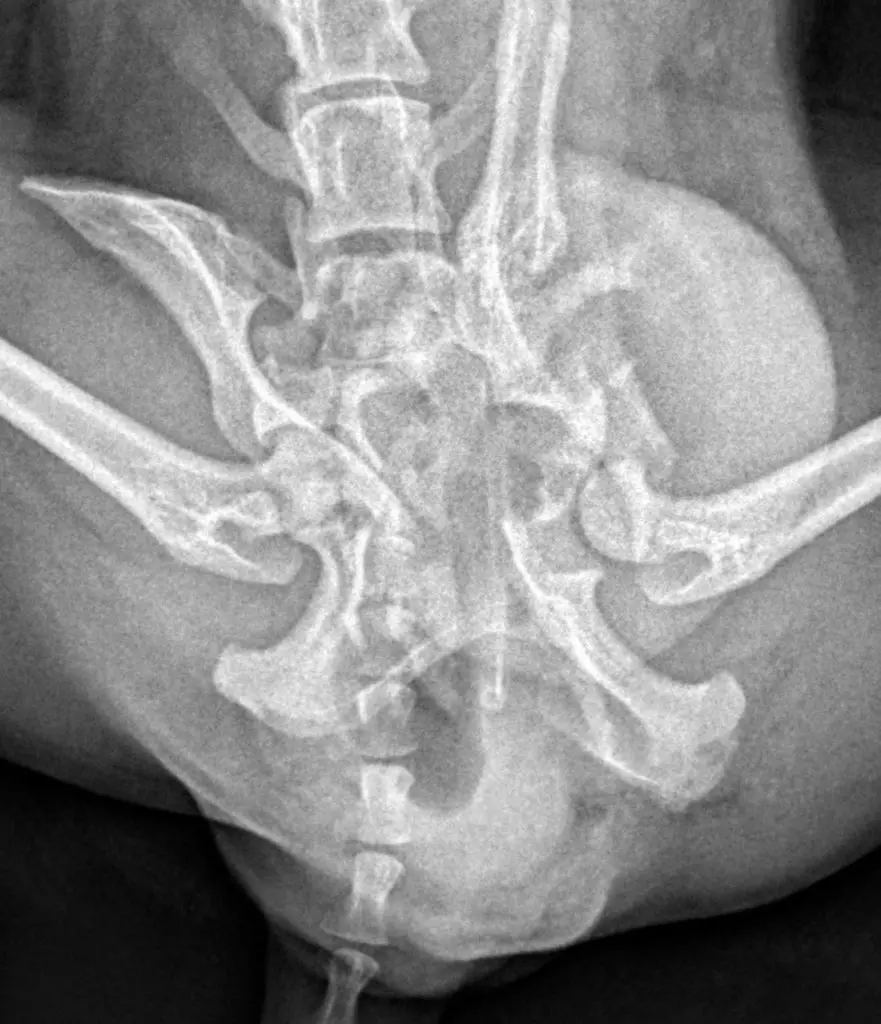

En primer lugar realizamos un completo examen ortopédico, en el que observamos una paraparesia no ambulatoria con incapacidad de mantener peso en la estación. A la palpación de la pelvis se puso de manifiesto dolor muy marcado, asociado a crepitación y una dismetría pélvica considerable.

Para obtener un diagnóstico definido, procedimos a realizar un protocolo diagnóstico completo, que incluyó un estudio radiológico y tomográfico de la pelvis. Gracias a las imágenes pudimos confirmar el diagnóstico, una fractura múltiple de pelvis con luxación sacroiliaca derecha, y luxación coxofemoral izquierda a consecuencia de una fractura conminuta del acetábulo.

Para poder definir con mas precisión todos los daños y establecer el mejor plan quirúrgico realizamos una tomografía computarizada (TAC) de la pelvis.